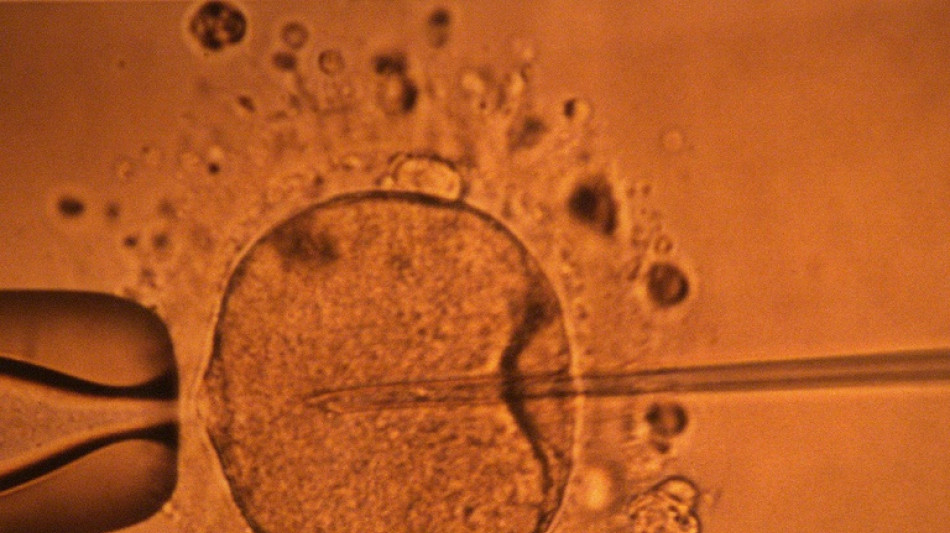

Un estudio apoya hipótesis de disminución mundial de concentración de espermatozoides / Foto: MARCEL MOCHET - AFP/Archivos